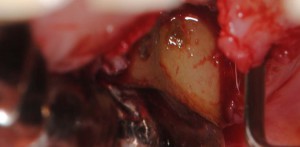

歯肉を開けると歯根表面に歯石を認めた

歯肉を開けると歯根表面に歯石を認めた